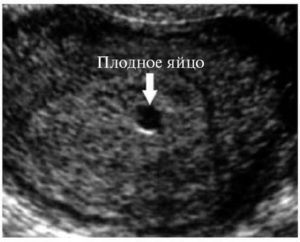

Существует расхожее мнение, что во время УЗИ-диагностики врач может перепутать плодное яйцо с наростом. Ведь при значительных размерах образований некоторые симптомы их нахождения в матке схожи с «интересным положением». Однако оно имеет под собой очень мало оснований.

Квалифицированный врач без труда отличит, полип или беременность он видит на мониторе приспособления. Плодное яйцо темного цвета и округлой формы, тогда как нарост светлый, имеющий цилиндрическую форму.

Отличить полипозное новообразование в матке от плодного яйца не составит труда – они отличаются как по форме, так и по цвету. Плодное яйцо более округлое и имеет темную окраску, а полип – более светлый.

Плодное яйцо — анэхогенное образование, то есть темное пятно круглой или овальной формы с четким контуром. Это потому что внутри содержится жидкость, в ней выделяется светлый эмбрион. Увидеть плод можно уже на 2 неделе.